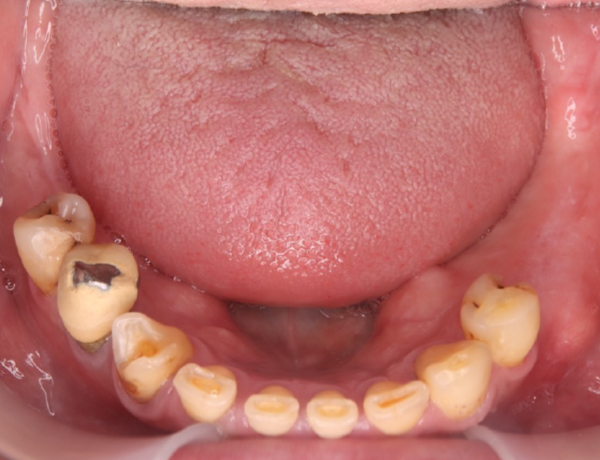

下あご

赤丸の部分は、骨隆起になります。下あごにも骨の隆起があります。

下あごには、入れ歯が入っていません。天然の歯が残っていますが、奥歯は何本か抜けてしまっている状態です。

こうしたアンバランスにより、上あごの入れ歯に負担がかかり歯が抜けている可能性も高いと判断しました。天然の歯にかぶせ物を行い、保険で下あごの入れ歯を作製しました。